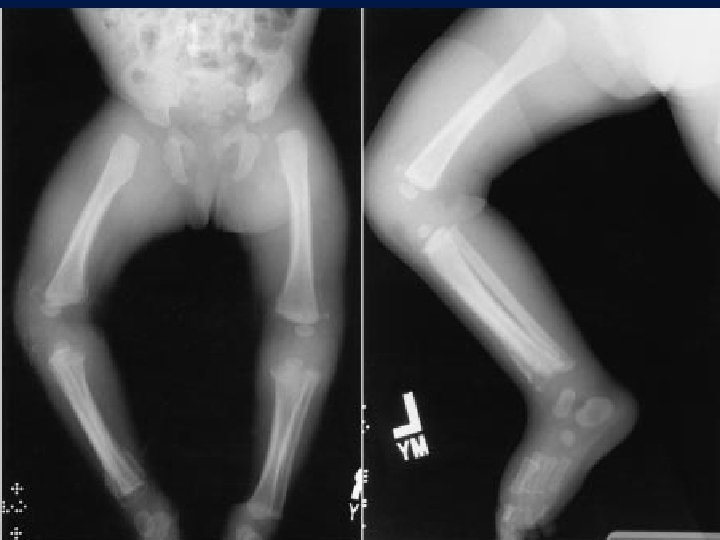

Fracture in children Fractures Caused by Child Abuse • Mostly occurs between birth and 2 years of age. • Multiple fractures in different stages of healing are almost always indicative of child abuse. • Multiple areas of large ecchymoses in different stages of resolution (from black and blue to brown and green) also are pathognomonic of child abuse.

Fracture in children • The most common sites of fractures caused by child abuse are the humerus, tibia, and femur • bone scan or a skeletal survey generally is indicated